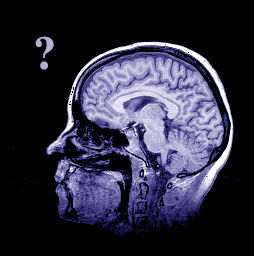

Clinical Case